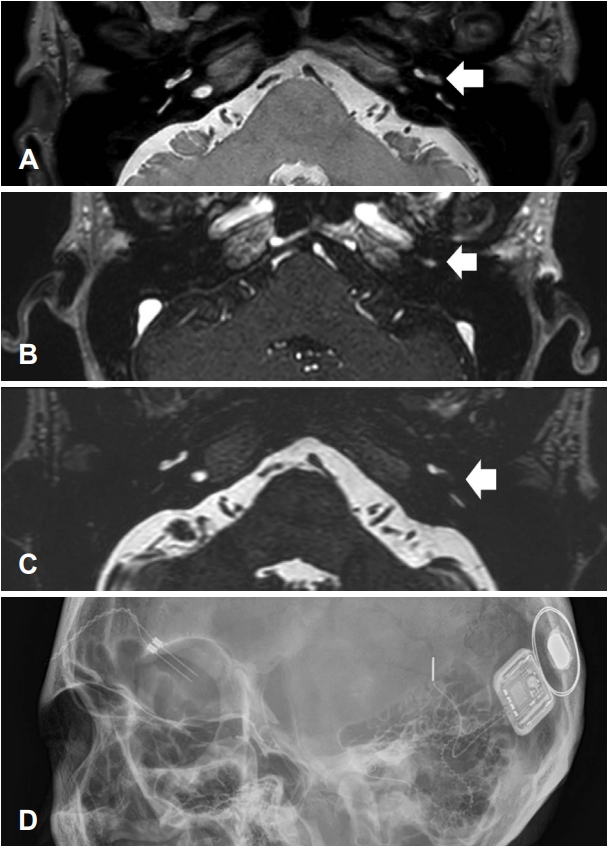

수술 전 재시행한 PTA에서 좌측 기도청력 94 dB HL, WRS는 최대 자극에도 8%였고, 우측 기도청력 7 dB HL로 좌측 전농 소견을 보였다(Fig. 1). 비디오 두부충동검사, 온도 안진검사상에서 특이 소견은 관찰되지 않았다. 수술 전 시행한 측두골 전산화단층촬영(temporal bone CT)에서 이상 소견은 없었으며, 본원에서 수술 전 와우와 청신경의 자세한 해부학적 특징을 확인하기 위해 시행한 조영 증강이 없는 proton-density (PD) weighted MRI에서 양측 청신경은 잘 관찰되었으나 좌측 와우 기저회전(basal turn)에 충만 결손이 확인되었다(Fig. 2). 보다 정확한 병변의 확인을 위해 과거 타원에서 촬영한 측두골 MRI를 환자에게 요청하여 확인한 결과, T1 강조영상에서 좌측 와우 기저회전에 가돌리늄 조영 증강이 되는 병소가 관찰되었으며, PD 및 T2 강조영상에서 저신호강도를 보이는 공간점유병소가 좌측 와우 기저회전에서 관찰되어 와우내 신경초종을 확인할 수 있었다(Fig. 2). 따라서 환자에게는 와우내 종양을 제거한 후에 인공와우 이식술을 시행할 예정임을 설명하였고, 수술을 시행하였다.

전신마취하 좌측 유양돌기 절제술(mastoidectomy) 및 후고실개방술(posterior tympanotomy)을 시행하여 안면신경와(facial recess)를 통해 접근하였고 정원창(round window)을 통해 와우내 종양을 확인할 수 있었다. 드릴을 이용하여 와우관을 따라 정원창의 위아래를 최소한으로 노출하여 종양의 경계를 충분히 확인하며 제거하였다(Fig. 3). 병변은 주로 고실계(scala tympani)에 위치하였고, 종양의 크기가 수술 전 촬영한 영상에서 4-5 mm로 추정되어, 일반적인 후고실개방술을 통해 정원창 주변의 시야를 충분하게 얻을 수 있었다. 와우의 추가 손상을 방지하고, 최소한의 노출을 통해 고실계에 존재하는 종양을 제거하기 위해, 정원창 부위의 와우벽을 점차적으로 제거하며 종양의 경계를 확인하였다. 이후 가장 작은 크기의 석션팁(suction tip)과 수직픽(right-angled pick)을 이용하여 종양의 경계를 확인하면서 종양을 정상 구조물에서 분리하여 제거하였고, 와우축(modiolus)은 보존되었다. 종양 제거 후 육안적 뇌척수액 유출의 소견은 없었으며, 인공 와우 전극을 개방된 와우의 고실계를 통하여 저항 없이 삽입하였다. 인공와우 전극은 정원창 주변 골조직을 제거하였기 때문에 직선형 전극(straight type)을 사용할 경우 와우축에서 너무 멀어지는 단점이 있을 수 있어, 와우축에 가깝게 전극이 위치할 수 있는 포옹형 전극(modiolus-hugging type)을 사용하였다. 종양 제거를 위해 개방된 전극 삽입 부위 주변의 와우 개창 부위를 연부 조직으로 막았다. 전극 삽입 직후 수술장에서 전극의 임피던스 값과 유발복합활동전위 (evoked compound action potential)의 역치값을 확인하였고, 22개의 전극 모두에서 정상 임피던스값과 역치값이 확인되었다. 수술장에서 시행한 두개골 엑스레이 검사상에서도 전극이 잘 삽입됨을 확인하였다(Fig. 2). 종양은 조직검사 결과상 신경초종으로 진단되었다(Fig. 3). 환자는 수술 후 4일간 주관적 어지럼을 호소하였으나, 수술 후 6일째 어지럼이 호전되고 수술 부위 상처에 특이 소견이 없어 퇴원하였다. 수술 3주 후 좌측 귀의 인공와우 착용 청력 역치는 24 dB HL로 개선되었고, WRS는 56%로 증가하였다. 수술 6주 후 청력 역치는 28 dB HL, WRS는 56%였고, 문장인지검사에서는 98%의 인지도 호전을 보였다(Fig. 1).

NotesAuthor Contribution Conceptualization: Hye Ah Joo, Hong Ju Park. Data curation: Hye Ah Joo. Formal analysis: Hong Ju Park. Investigation: Hye Ah Joo. Methodology: Hye Ah Joo, Hong Ju Park. Project administration: Hong Ju Park. Resources: Hong Ju Park. Supervision: Hong Ju Park. Writing—original draft: Hye Ah Joo. Writing—review & editing: Hye Ah Joo, Hong Ju Park. Fig. 1.PTA of the patient with left intracochlear schwannoma. Preoperative (gray) and six-week postoperative (black) PTA. PTA, pure tone audiometry. Fig. 2.Preoperative MR images and intraoperative simple X-ray. A: Space occupying lesion (arrow) in basal turn of left cochlea on proton-density weighted image. B: Enhanced mass (arrow) was identified in basal turn of left cochlea on T1-weighted, Gd-enhanced image. C: The defect (arrow) in the high signal intensity of the cochlea filled with fluid was identified in basal turn of left cochlea on T2-weighted image. D: Skull X-ray showing the inserted perimodiolar electrodes of the cochlear implant. Fig. 3. Intraoperative microscopic views of the tumor and histologic findings. A: After posterior tympanotomy, round window was identified. B: The arrow indicates intracochlear mass in the scala tympani exposed after the bony drilling below the round window along the cochlear basal turn. C: Widely opened cochlear basal turn after the mass had been removed completely. D: The tumor has typical histologic features of the schwannoma. The arrow indicates compact hypercellular Antoni A area and the arrowhead indicates myxoid hypocellular Antoni B area. (×100, hematoxylin and eosin stain). REFERENCES1. Kennedy RJ, Shelton C, Salzman KL, Davidson HC, Harnsberger HR. Intralabyrinthine schwannomas: Diagnosis, management, and a new classification system. Otol Neurotol 2004;25(2):160-7.